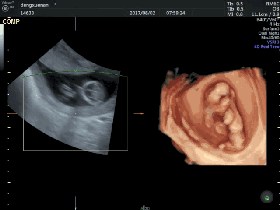

1.四维彩超的检查目的

通过四维超声检查,能够准确反映出胎儿生长发育情况,多角度、多方位进行胎儿异常评估。包括先天疾病。如胎儿唇腭裂、四肢发育畸形、脑膜膨出、脊柱裂、腹壁裂等先天畸形。

▶监测胎宝宝的生长发育

检测胎宝宝发育是根据测量胎宝宝各部门的数值来判断的,如胎头双顶径等。

▶胎宝宝是否畸形

四维彩超检查是发现胎儿畸形的一个重要手段。一旦发现胎儿畸形,就可以及时终止妊娠!

▶测量羊水量

四维彩超可以比较准确地测量羊水量。母体羊水量的多少对胎儿的发育非常的重要,因为羊水太多或者太少都会导致胎儿畸形。

▶了解胎盘位置

在彩超中也可以清楚地了解胎盘的位置是否正常,胎盘是否有血管瘤的存在、是否成熟等,可以明确地诊断出前置胎盘,胎盘早剥等危险情况的存在。